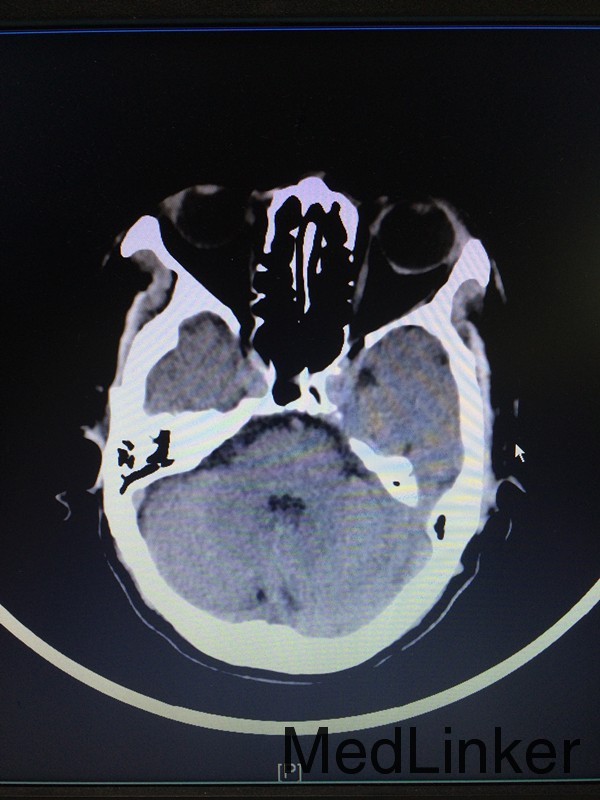

主诉:左侧肢体乏力28天 病史:患者60岁男性,于入院前28天无明显诱因出现左侧肢体乏力,伴言语不清,表现为行走不稳、神志模糊,较烦躁,无头痛、头晕、恶心呕吐等,于当地医院行头颅CT提示:大脑中动脉高密度影。患者第二天出现头痛伴呕吐,急查头颅CT提示:大面积脑梗。

查体:左侧上肢2级,下肢2级,右侧肢体肌力正常 辅助检查:查头颅CTA提示:右侧额叶及岛叶(包括基底节)脑梗塞,轻度脑萎缩,CTA未见明显异常

诊断:右侧额叶及岛叶大面积脑梗塞 治疗:予活血化瘀、改善血管痉挛、脱水降颅压等治疗,并申请康复、高压氧等治疗。

随访:患者病情缓解出院 讨论:患者60岁男性,突发大面积脑梗塞,可能是由脑动脉主干阻塞所致,CT呈现大片状低密度阴影,多为脑叶或跨脑叶分布,脑组织损害范围较大,临床上除表现脑梗塞的一般症状外,还伴有意识障碍及颅内压增高。不排除为体循环的血栓掉落至大脑动脉引起。